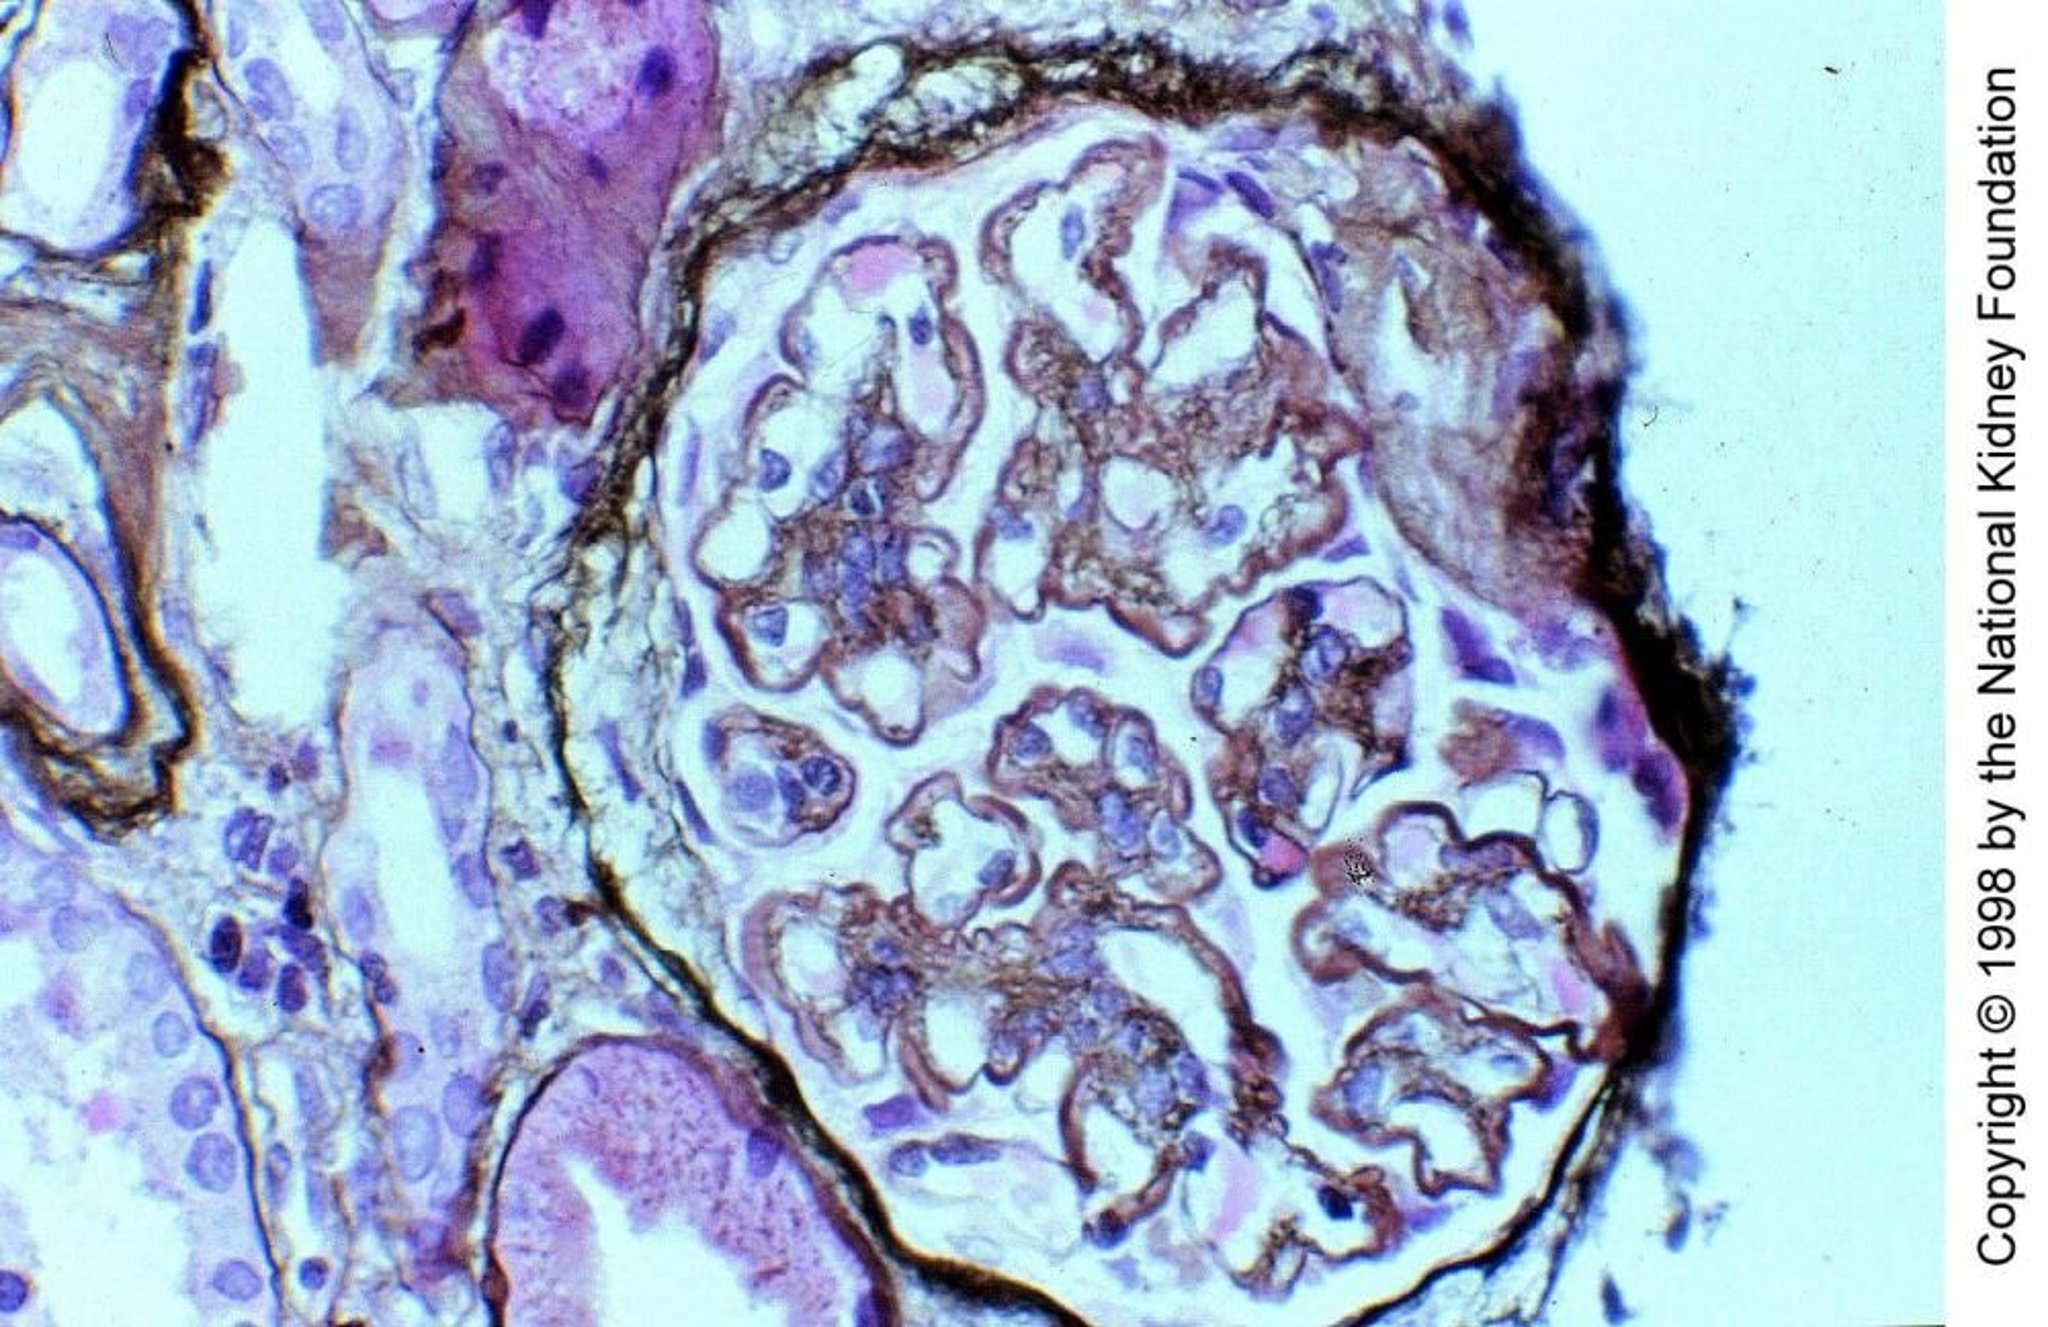

膜性増殖性糸球体腎炎,補体介在型

補体介在型の膜性増殖性糸球体腎炎(MPGN)II型では,糸球体毛細血管壁およびメサンギウム領域において,C3腎炎因子(C3からC3bに直接開裂することでプロパージンのように機能するIgG自己抗体)が副経路を介して補体を活性化させる。C3沈着物が部分的に基底膜の基底板を置換することで,基底膜が肥厚し,顕著なリボン状の外見をもたらしている(PAM染色,400倍)。